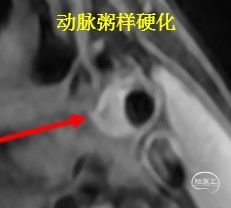

但是,高分核磁显示,第一个是“烟雾病”,第二个是“动脉粥样硬化”。

病例甲的高分核磁:显示右侧颈内动脉末端向心性狭窄,内膜增厚,无强化,符合烟雾病的表现。

病例乙的高分核磁:右侧大脑中动脉M1段呈偏心狭窄,斑块呈等T1信号,增强扫描后明显强化。

左侧大脑中动脉M1段存在下壁等信号斑块。

复习:高分核磁对烟雾病和动脉粥样硬化的鉴别诊断:

烟雾病:向心性狭窄,强化或不强化

动脉粥样硬化斑块:偏心性狭窄,T2可呈高信号,强化或不强化